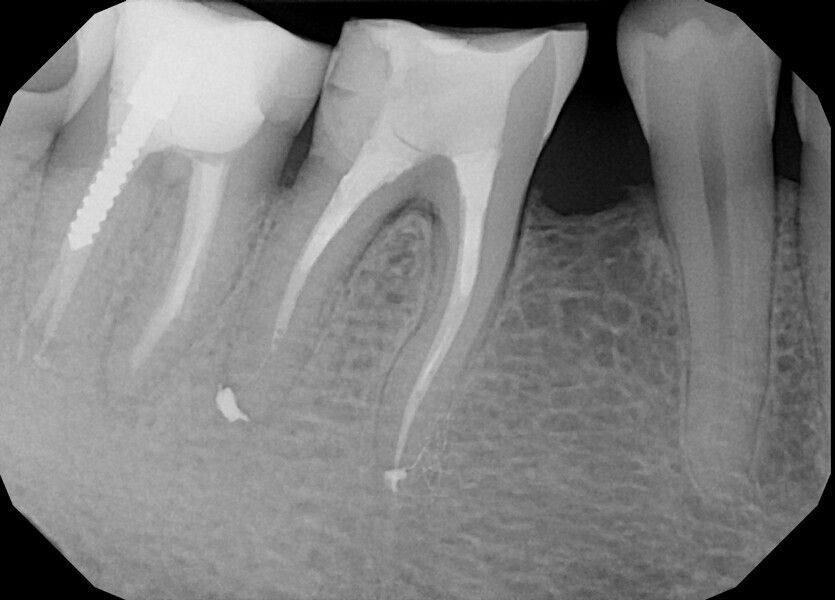

A 40-year-old female patient was referred to Dr Karaś’s office because tooth #47 was symptomatic and tender to percussion. During examination with a conventional radiograph, the referring dentist could not find any visible signs of the root canals, so he would not have been able to shape the root canals properly.

During the consultation appointment, a CBCT scan was performed. It revealed a small osteolytic lesion around the mesial root, suggesting the possibility of achieving patency in the root canals in the mesial root. Around the distal root, there were no signs of the lesion, which indicated that the mesial root was the cause of the symptoms. The radiographic examination also revealed a broken lentulo in the MB canal (Fig. 16).

Figs. 16 a & b